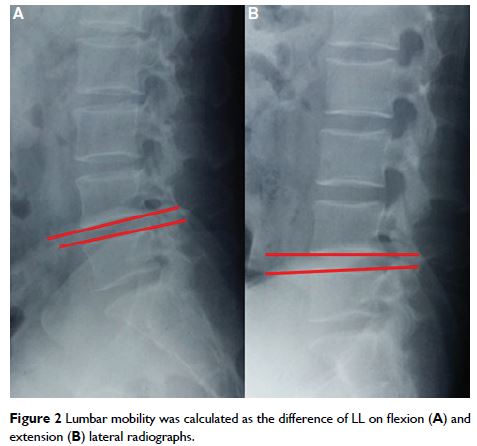

腰椎间盘突出后路减压及融合术后,持续性腰背痛的发生率和危险因素

- 作者:Hui Wang, Tao Wang, Qian Wang, Wenyuan Ding

- 期刊:Journal of Pain Research